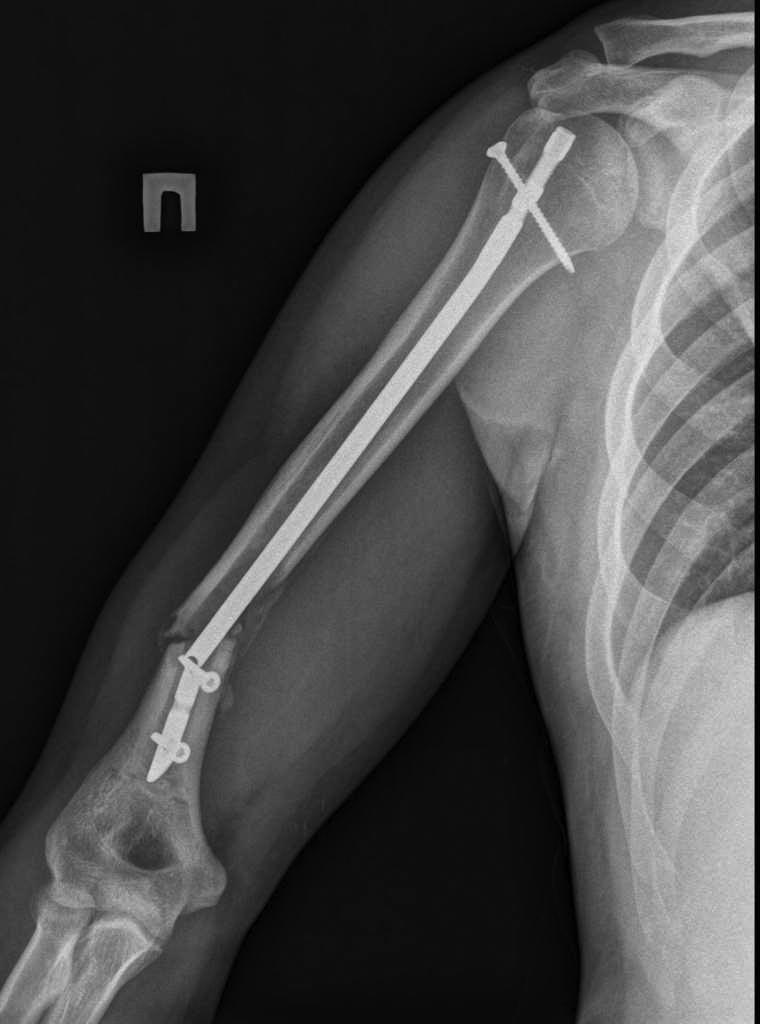

> Здравствуйте уважаемые форумчане. Представляю Вашему вниманию очередной

> сломанный

> штифт. Пациент 25 лет, в сентябре 2012 г ДТП. Кроме всего прочего,

> открытый перелом правого

> плеча с дефектом костной ткани. При поступлении выполнено ПХО и ЧКО из 2

> колец. После

> заживления раны выполнен БИОС плеча. Штифт сОлидный, Остеомед. Пару дней

> назад во время

> попытки открытия крышки банки (нагрузка по ротации) почувствовал боль в

> плече. Результат на

> снимке. Планируем удалить оба отломка (дистальный открыто) и

> перештифтовать более

> массивным штифтом. Вопрос 1: есть ли вариант в данном случае закрыто

> удалить дистальный

> франгмент НЕканюлированного штифта. Особых инструментов для удаления

> сломаных штифтов не

> имеем. Вопрос 2: как вариант рассматриваем выполнить ЧКО удалив

> предварительно только

> проксимальный фрагмент штифта. СтОит ли? Вариант накостного остеосинтеза с

> пластикой и без

> не рассматриваем. Спасибо за внимание.